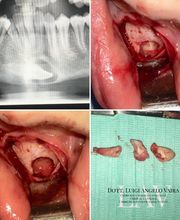

Dott. Luigi Angelo Vaira - Chirurgia Maxillo-Facciale

Il dott. Luigi Angelo Vaira si è laureato in Medicina e Chirurgia presso l'Università degli Studi di Sassari il 25 luglio 2011. Il 13 luglio 2017 ha conseguito la specializzazione in Chirurgia Maxillo-Facciale presso lUniversità di Napoli Federico II. Negli ultimi 5 anni si è interessato e occupato di tutte le principali patologie del distretto testa-collo: traumatologia, oncologia, ricostruttiva, estetica e malformativa. Ha gestito in prima persona l'ambulatorio di Day Surgery maturando, negli ultimi 5 anni, un'esperienza di oltre 1500 interventi di chirurgia orale avanzata, preprotesica ed implantologica, chirurgia estetica del volto e dermatochirurgia. Si è inoltre specializzato nel trattamento funzionale e chirurgico conservativo dei disordini temporo-mandibolari e della gestione dei pazienti con problematiche legate a osteonecrosi da bifosfonati e da radioterapia. Da luglio 2017 svolge attività libero-professionale e di consulenza presso studi odontoiatrici e dermatologici. Da Aprile 2018 è assunto come dirigente medico presso l'U.O.C. di Chirurgia Maxillo-Facciale dell'A.O.U. di Sassari.